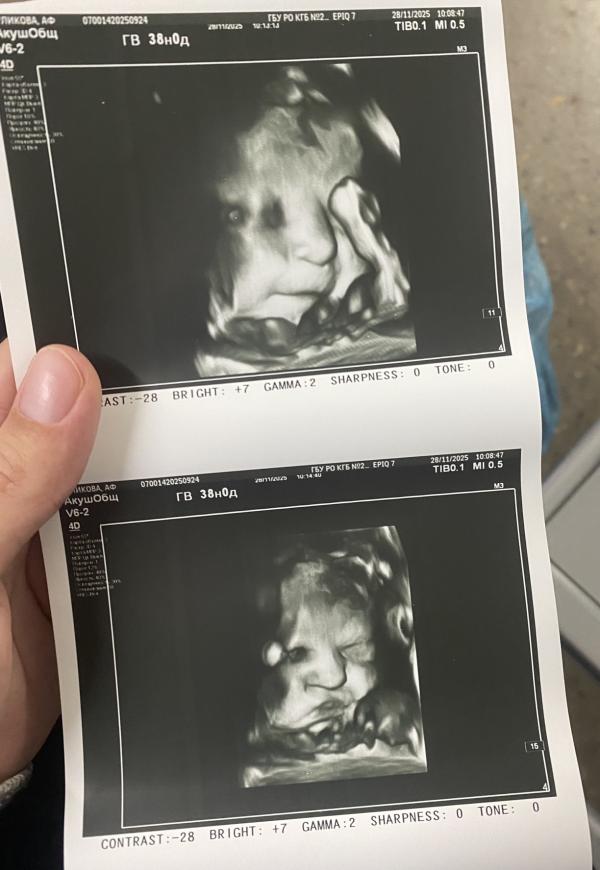

Итого: крайнее узи и он решил все же показать личико

Все может быть, я даже не надеялась, а мне фоток сделали прям прикольных

Ух, какой сладкий 🥰